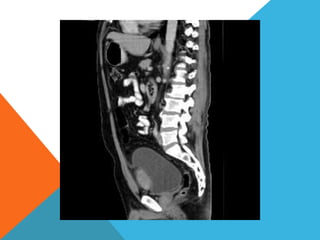

El paciente presentó síntomas de sangrado digestivo y pérdida de peso. Exámenes revelaron gastritis crónica asociada a H. pylori. Un tumor fue descubierto en una colonoscopia normal. La cirugía removió un tumor fibroide solitario, una rara neoplasia mesenquimal que usualmente crece lento y tiene bajo potencial de malignidad. El pronóstico después de la remoción quirúrgica es generalmente bueno.